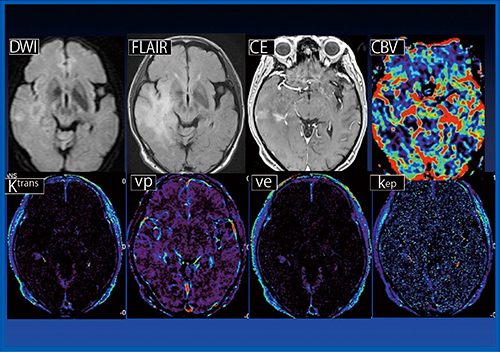

症例3(図3)は,LGG(グレード2)である。右側頭葉に高信号に造影される領域が認められ,術前診断では一部HGGが疑われたが,Ktransは低値でありLGGを示唆していた。

図3 症例3:LGG(グレード2)(70歳代,男性)